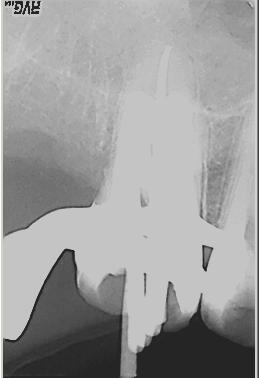

Röntgenmeßaufnahme

Röntgenmeßaufnahme nach vorgängig durchgeführter endometrischer Längenbestimmung